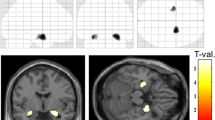

Diffusion weighted MRI (DWI) and Fixel-based analysis (FBA) with pathology correlations. Linear regression analysis of DWI measures averaged across either all core or deep white matter regions (also regressed using Z scores relative to control DWI data, where shown) against pathology variables in same regions (as mean scores and Z scores compared to control cases); data is shown where significant regressions were identified on univariate analysis (See also supplemental Table 3): (A) Iba labelling and AD, MD, RD (core white matter), (B) Iba1 and MD (deep), (C) Phospholipid protein (PLP) and FA, AD (core), (D), PDGFRβ Labelling index (LI) and MD, RD (core), (E) PDGFRβ type 2 vascular density and FA (core), (F) SMA type 2 vascular density and Fixel (Core), (G) perivascular space measurement (PVS) and FA (Deep) (H) COL4 vascular diameter and AD and MD (Core) (I) COL4 vascular diameter and AD and MD (Deep). These confirmed the main associations for DWI and FBA with pathology were in the core white matter and for vascular pathology measures (see text for details). Pipeline for the DWI analysis: (J) Diffusion images following denoising, un-ringing, motion, eddy and field bias corrections were aligned to T1 and diffusions interpolated to match voxel size of T1 (1 mm). (K) Middle temporal gyrus (MTG) was rotated to align flat to enable orientation with brain slice, (L) Regions of interest (ROI) in white matter (superior temporal gyrus green shades, middle temporal gyrus blue shades, inferior temporal gyrus red shades with deeper colour shade representing deep ROI) were best matched and co-registered on MRI and pathology histological sections using Freesurfer white matter parcellation to manually segment gyri into the core and deep white matter (note the histology sections shown for illustration only or MRI and not aligned to MRI slice axis shown). (M) MRI images were then rotated back to extract diffusion tensors for each region. (N) Fixed-based-analysis (Left to right): 1. Individual orientation distribution function (ODF) were calculated, 2. registered to create a healthy population template, 3. which was used to create a SIFT filtered tractogram, for 4. Fixel-based analysis. RD = Radial Diffusivity, AD = Axial Diffusivity, MD = Mean Diffusivity, FA = Fractional Anisotropy, FIXEL = Fixel Based Analysis Measurement, LI = labelling index

Correlations with microvascular pathology and neuropsychology. (A-F). Logistic regression analysis of pathology measures in groups with and without pre-operative verbal cognitive decline (see also Supplemental Table 4) showing significant differences in vascular pathology measures in the decline group, represented graphically as box plots (median, 25th and 75th centile, range): (A) Perivascular space (PVS) and (B) SMA type 2 vascular density were increased in the decline group whereas (C) SMA type 1 vessel diameter (deep) (D) PDGFRβ type 1 vessel diameter (deep), (E) PDGFRβ type 2 vessel diameter in core and (F) deep white matter were significantly lower in the decline group. (G). Summary diagram based on all observations of regional alterations and relationship of small vessels measurements with other cellular components in TLE white matter (blue text and arrows) and which factors might impact on DWI changes (purple arrows) and cognition (brown). In brief, temporal lobe epilepsy is associated with both increased arteriolosclerosis and vascular pericytes; the later may represent a protective adaptation. Increased parenchymal PDGFRβ cells, which correlate with degenerative vascular sclerosis, are increased particularly in the deep white matter. Epilepsy is associated with white matter oligodendrogliosis and microglial increase, the latter particularly in deep regions. Increased perivascular space and reduced small vessel size are linked to cognitive decline. DWI alterations in the core are mainly influenced by increased glia density, PVS and small vessel changes. Icons created with Biorender

White matter pathology and neuropsychometry

Nine of 43 patients were classified as having verbal decline in cognitive function pre-operatively and 9/43 had impaired working memory at the time of surgery. Using logistic regression analysis for mean deep and core white matter values for groups with or without cognitive decline, we found higher PVS measure (Fig. 5A) and SMA type 2 vessel densities (Fig. 5B) in the decline group, as well as reduced vascular diameters for deep type 1 vessels (SMA and PDGFRβ) and type 2 vessels in core and deep (PDGFRβ) (Fig. 5C–F). There was also a trend for lower MAG LI (Supplemental Table 4). There were no significant relationships for pathology variables and working memory impairment at the time of surgery. These findings support a relationship between microvascular alterations, including vessel calibre in those patients with TLE who have declined in their general verbal intellect over time prior to surgery.